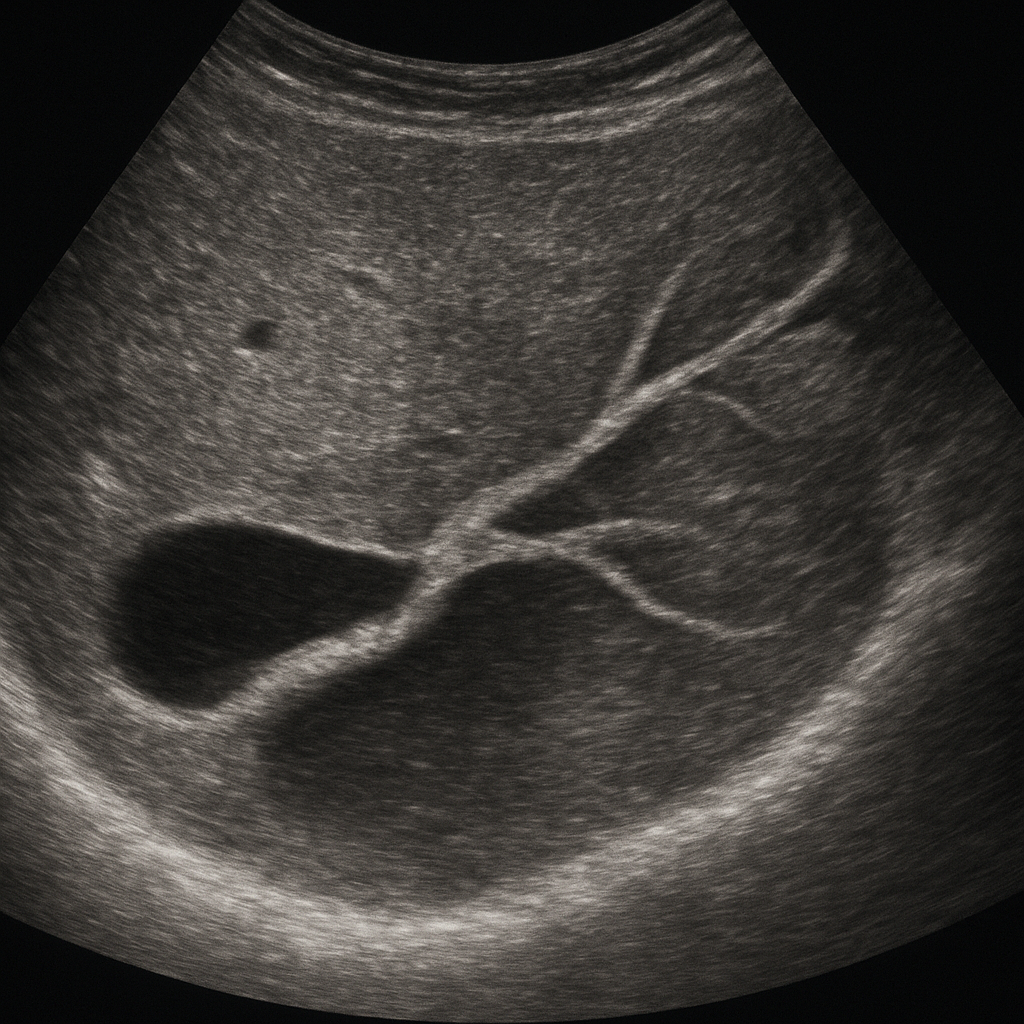

Podstawą skutecznego badania USG jest znajomość anatomi dróg żółciowych i prawidłowe przygotowanie pacjenta. Przewody żółciowe można podzielić na wewnątrzwątrobowe i zewnątrzwątrobowe. Wewnątrzwątrobowe odprowadzają żółć w głąb wątroby, łącząc się ostatecznie w przewód wątrobowy prawy i lewy, które tworzą przewód wątrobowy wspólny. Następnie łączy się on z przewodem pęcherzykowym, tworząc przewód żółciowy wspólny.

Badanie ultradźwiękowe układu żółciowego wykonywane jest za pomocą głowicy o częstotliwości zazwyczaj 3,5–5 MHz. Pacjent leży płasko lub w pozycji na boku, a lekarz aplikuje na skórę specjalny żel, poprawiający przewodzenie fal ultradźwiękowych. Ważne jest dokładne odwzorowanie przewodu żółciowego wspólnego oraz pęcherzyka żółciowego w układzie podłukowym i międzyżebrowym.

• Średnicę przewodów wewnątrz- i zewnątrzwątrobowych (norma do 4 mm)

• Grubość ściany pęcherzyka żółciowego (norma do 3 mm)

• Obecność złogów czy kamieni w świetle pęcherzyka i przewodów

• Cholestaza wewnątrzwątrobowa – poszerzenie przewodów wewnątrzwątrobowych, obraz „drzewka porowatego”.